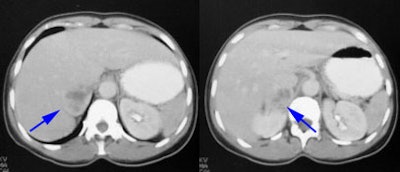

Pheochromocytoma: The patient was discovered to have a right adrenal mass (blue arrows) during a CT evaluation for ovarian carcinoma. Further clinical and laboratory evaluation revealed the patient to be hypertensive with elevated urinary catecholamines. The MIBG exam demonstrated intense tracer accumulation in this lesion (black arrows) which was proven to be a pheochromocytoma. No other lesions were identified. Thyroid activity can be seen due to inadequate thyroid blocking with SSKI drops. |